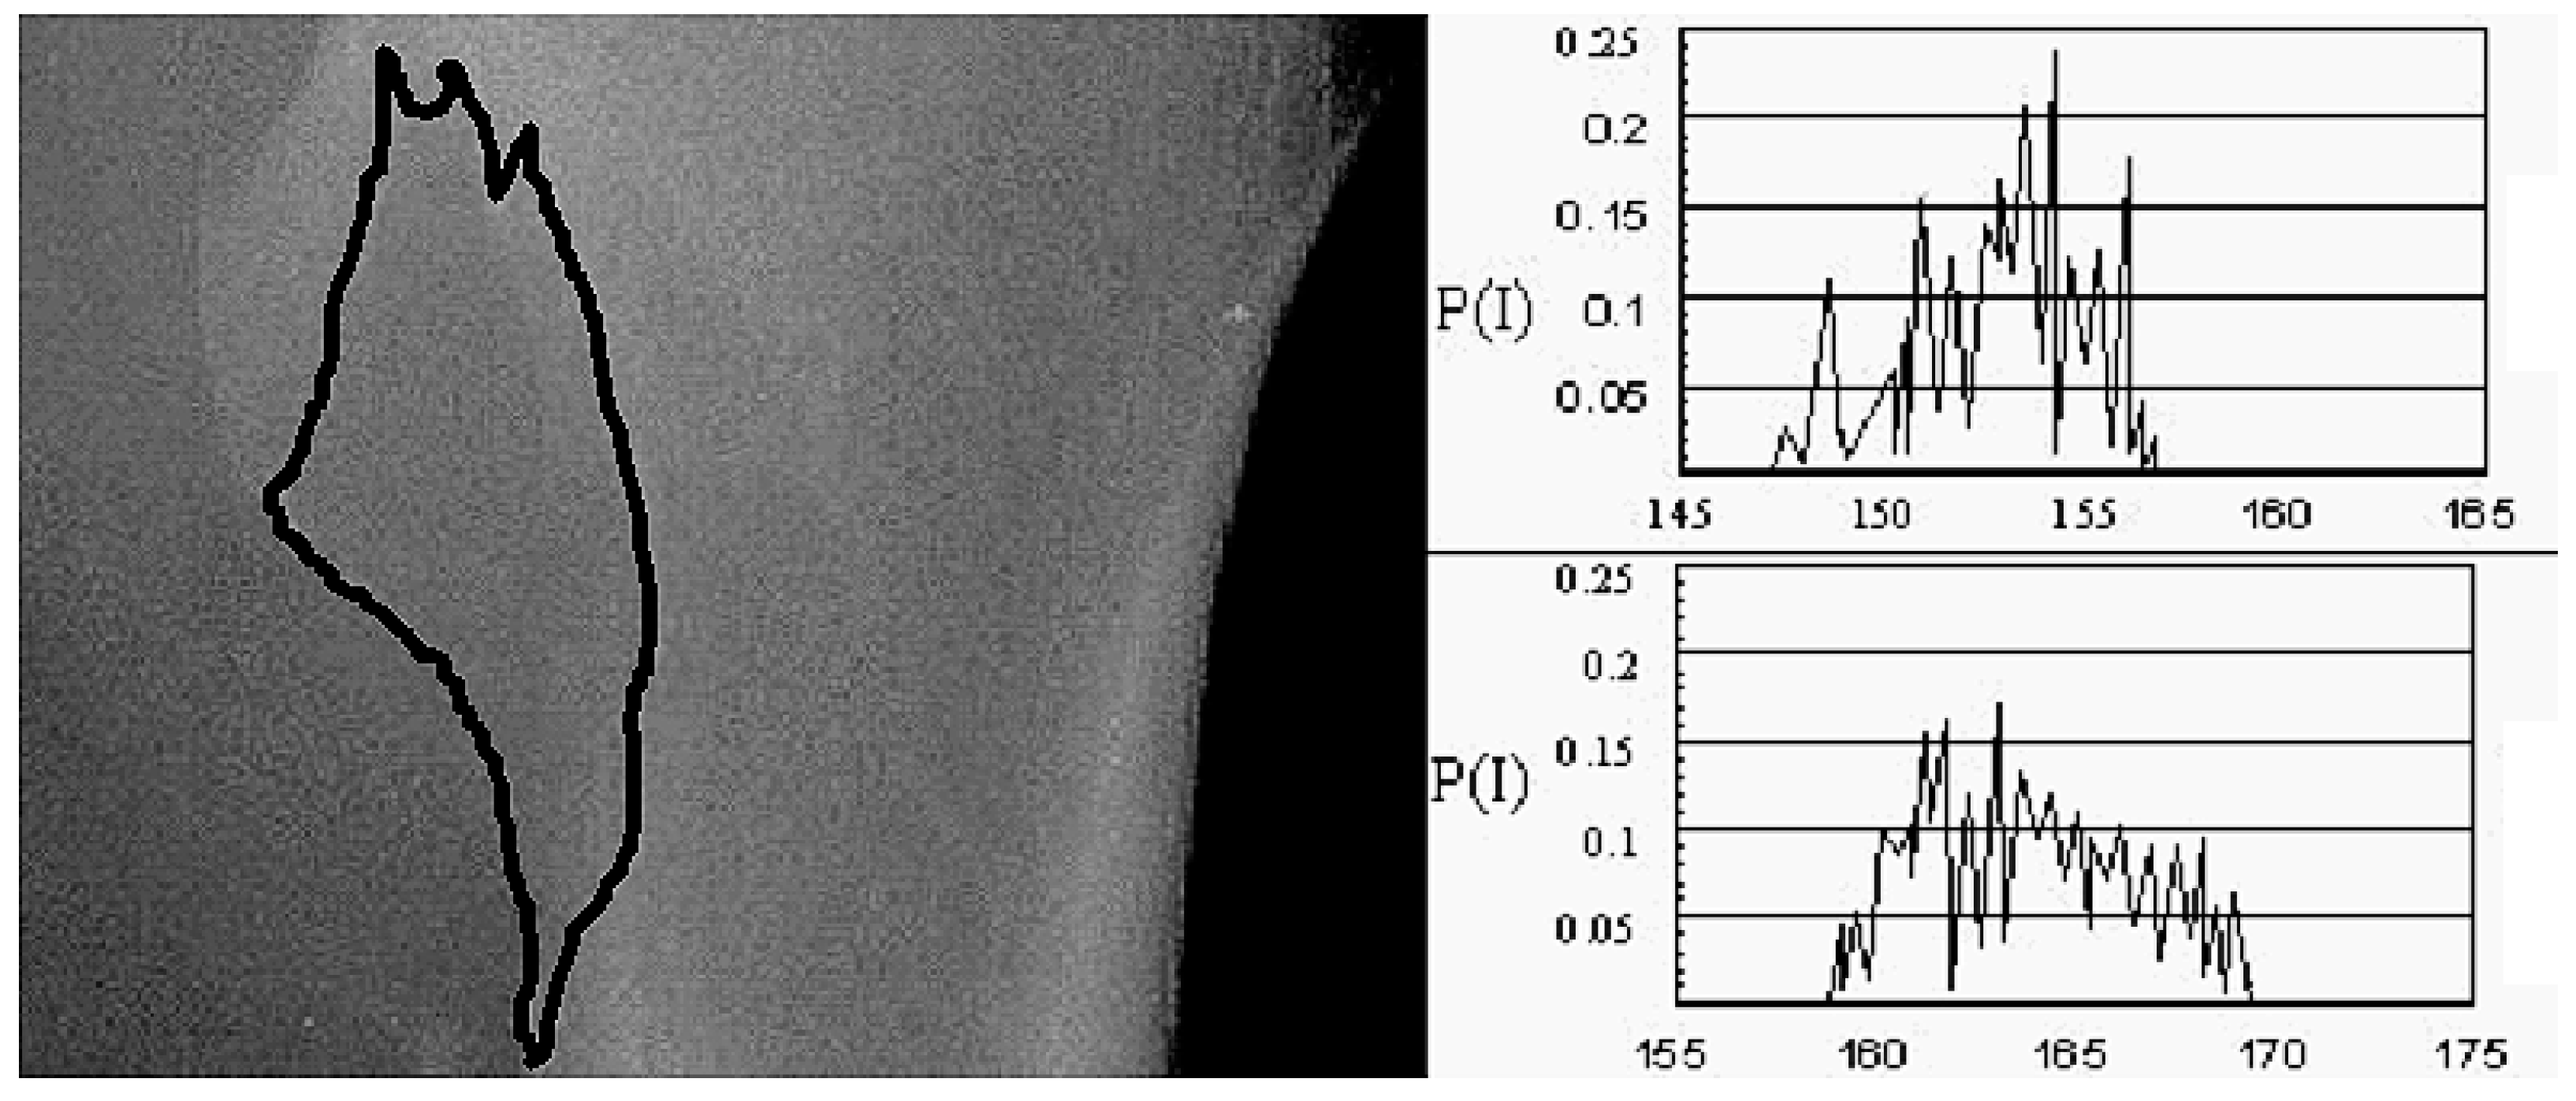

Using pain relief as a measure of response to treatment is subjective and in the case of metastatic bone disease the need for an objective, reproducible marker as in other solid organs is evident. The RECIST criteria that are used for the evaluation of treatment outcome in solid tumors are based mainly on Computerized Tomography (CT) imaging and offer specific guidelines for the quantitative measurement of tumor response [21], offering the clinicians an important tool on the pathway of decision-making for the patient’s management. Bone lesions are considered “non-measurable” according to the RECIST criteria, especially sclerotic ones. Therefore, the use of image processing to assess the effect that radiotherapy has on affected bones seems to be the question that needs to be answered. Plain imaging, by means of conventional X-rays, was used by Kouloulias et al. for the evaluation of recalcification of osteolytic bone metastasis in patients with breast cancer that received the combination of radiotherapy with disodium pamidronate (DP) [22,23]. Plain radiographs were taken at baseline and two weeks after each i.v. infusion of DP, using the same settings for the exposure. The quantitative assessment of bone change was based on measuring the first-order statistics of the mean value and energy of gray-level histograms (MVGLH-μ and EGLH-e, respectively) in the osteolytic region. The quantitative assessment of bone loss was obtained using the mean value and energy in terms of the first-order statistics, as defined below.

If n(I) is the number of pixels whose intensity is I and N is the total number of pixels in the region of interest, then the occurrence probability of intensity I is:

P ( I ) = n ( I ) N

At eight-bit gray-level quantization, the resulting distribution takes the form of a first-order histogram with 256 bins, where each bin is one of the integer sample values I = 0, …, 255.

Then the mean value of the gray-level histogram (MVGLH) is assessed as:

μ = I = 0 255 I ( P I )

estimating the value around which central clustering occurs.

Next, the energy of the gray-level histogram (EGLH) is assessed by:

energy = I = 0 255 P ( I )

As mineral is lost from the lytic metastases, the distribution of pixel intensities is shifted and becomes more concentrated at the lower gray levels. As a result, the mean value decreases and the energy increases in the osteolytic regions. After the evaluation of the images by expert radiologists, significant changes were detected. In detail, there was an 11.08% (95% CI 10.21, 11.93) mean reduction of energy in the gray-level histogram and an 11.63% (95% CI 10.96, 12.29) increase in the mean value of the gray-level histogram, showing a radiological improvement (Figure 1). However, there are some limitations in the use of plain radiographs and MVGLH and EGLH, especially in the case of the thorax and the abdomen where there are superimposed movable tissues. The deviation in MVGLH was studied after sequential radiographs were taken using the same settings and it was found to be higher in areas of the thorax (21.2%) and the abdomen (42.4%), while the deviation in weight-bearing bones was a maximum of 2.9% [24]. The use of an image-processing method that could offer quality assurance and reproducibility, by means of CT images that are used for solid organs, seems appealing.

Figure 1. First-order statistics as an image processing technique for the evaluation of recalcification of bone lytic metastasis at the femur after radiotherapy. Mean value and energy (MVGLH, EGLH) at baseline (EGLH = 0.19, MVGLH = 155.1) and six months after initiation of multimodality treatment (EGLH = 0.17, MVGLH = 173.3). P(I) refers to the probability of intensity (I).